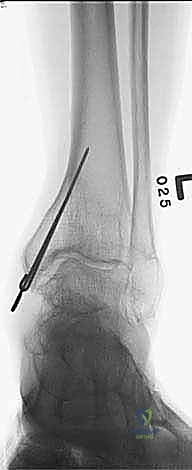

المرحلة الثانية: تركيب المثبت الخارجي (Frame Application)

قبل قطع العظم، يقوم الدكتور هطيف بتركيب الهيكل الخارجي (الإليزاروف أو الفريم الدائري).

1. يتم إدخال أسلاك دقيقة جداً (K-wires) ومسامير نصفية (Half-pins) عبر الجلد إلى العظم بدقة متناهية لتجنب الأعصاب والأوعية الدموية.

2. يتم تثبيت هذه الأسلاك في الحلقات المعدنية الخارجية. حلقة أو حلقتين فوق مكان القطع المخطط له، وحلقة تحته (في الجزء السفلي من الساق والقدم إذا لزم الأمر).

3. يتم التأكد من استقرار الهيكل الخارجي بالكامل.